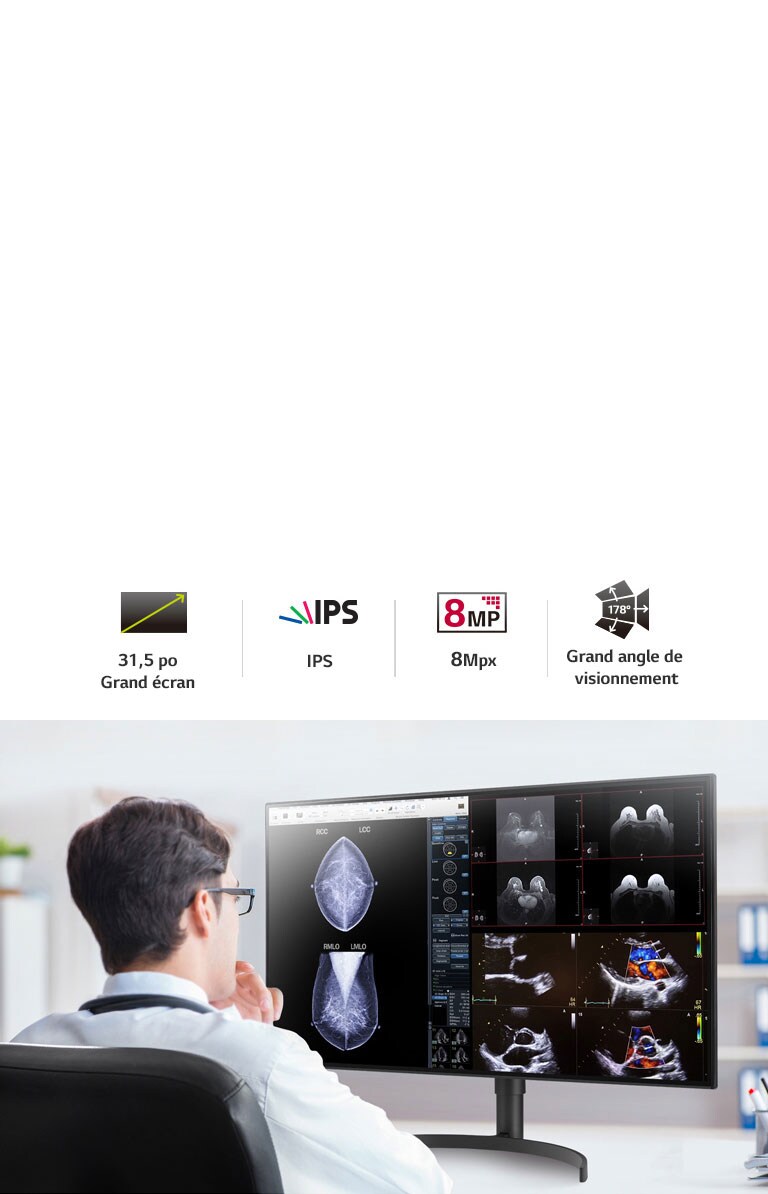

- Écran IPS 8 Mpx de 31,5 po

- Mode multi résolution